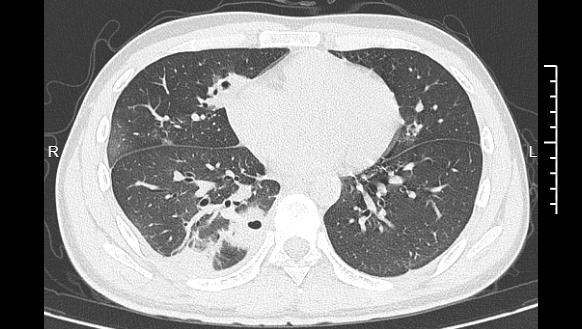

熬到第三天沪深投,小林已经烧到39℃,赶紧来到医院就诊。接诊的丁群力主任医师一看他的症状,立刻安排了CT检查。结果显示:小林的肺里有十几个空洞,部分肺组织已经坏死,这是典型的血源性肺脓肿。进一步的细菌培养和基因检测揭开了真相,小林的血液里检出了金黄色葡萄球菌,这种细菌就藏在每个人的皮肤表面。“罪魁祸首”就是那颗被挤掉的痘痘。丁群力解释说,这颗痘痘长在脸部“危险三角区”,挤痘痘时的压力把细菌推进了血管,引发了败血症,接着细菌顺着血流跑到肺部,侵蚀肺组织。